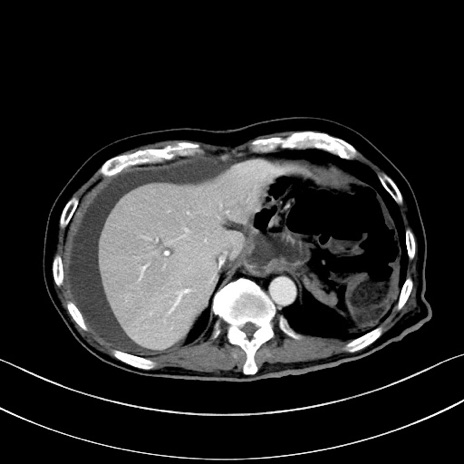

症例28(横断像)

【症例】60歳代男性

【主訴】嘔吐

【現病歴】胃癌にて胃全摘後。食思不振が悪化し、夜中に嘔吐することがある。

【既往歴】胃癌、胃全摘、脾摘、胆摘後

【データ】WBC 5900、CRP 10.56